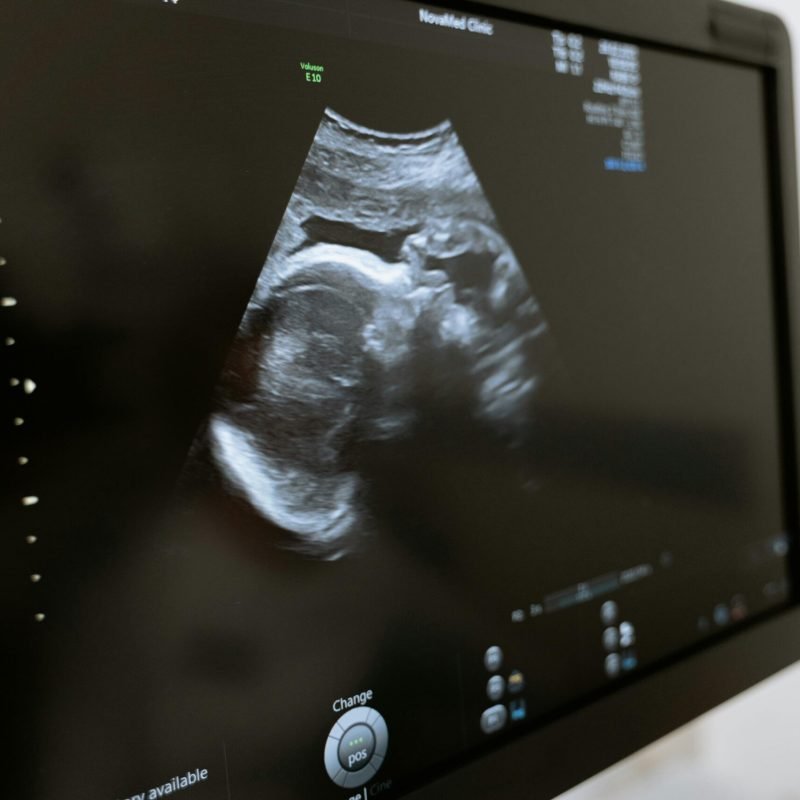

Specializimi në obstetrikë përqendrohet në kujdesin shëndetësor të gruas gjatë shtatzënisë, lindjes dhe periudhës pas lindjes, duke përfaqësuar një shtyllë themelore të shëndetit të nënës dhe foshnjës. Obstetrët luajnë një rol jetësor në monitorimin e zhvillimit të shtatzënisë, diagnostikimin dhe menaxhimin e komplikacioneve, si dhe në ofrimin e kujdesit të sigurt dhe të personalizuar gjatë procesit të lindjes. Ky kujdes përfshin ndjekjen e rregullt prenatale, mbështetjen mjekësore dhe emocionale të gruas shtatzënë, këshillimin për një shtatzëni të shëndetshme dhe kujdesin pas lindjes, me fokus në rikuperimin e nënës dhe mirëqenien e foshnjës. Obstetrika pasqyron një angazhim të vazhdueshëm për të garantuar sigurinë, shëndetin dhe përvojën pozitive të gruas në një nga fazat më të rëndësishme të jetës së saj.